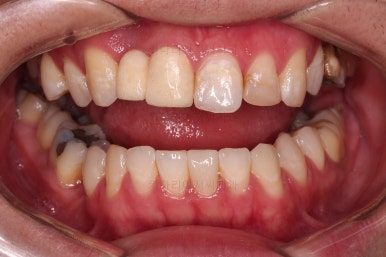

임플란트 완료시 모습인데요.

임플란트 식립부터 완료까지 시간이 걸리다보니 최종 종료까지는 총 19개월이 걸렸습니다.

교합도 잘 맞고 임플란트도 잘 완성되었네요.

매복치아도 손상 없이 잘 배열이 되었고, 교합도 좋게 마무리 되었습니다.

전후 비교입ㄴ디ㅏ.

크게 바꿀 필요가 없었던 얼굴모습은 거의 그대로 유지를 했고요. 웃을 때의 치열의 정렬된 느낌은 개선되었습니다.

매복치, 유치, 결손치 등 기능적인 부분들이 모두 잘 개선되었습니다.